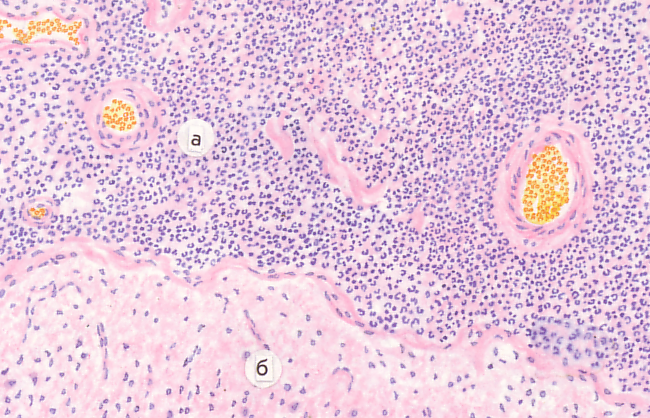

Микроскопический взгляд на мишитарный туберкулез легкого: фотодокументация